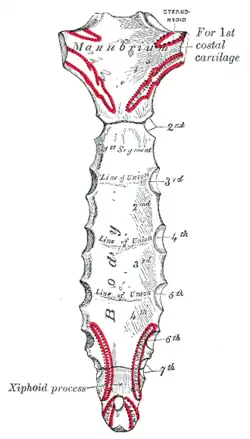

Posterior surface of sternum. (Xiphoid process labeled at bottom.) | |

Structure

The xiphoid process is anatomically situated at the level of the 9th thoracic vertebra (T9) and corresponds to the T7 dermatome.